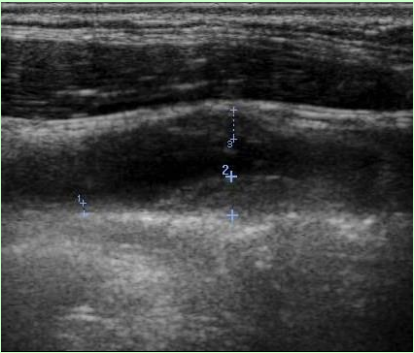

正常乳腺は皮下脂肪組織内に白い部分として描出されます。一般に表面から表皮層、浅在筋膜浅層の白い線が描出され、そこからクーパー靭帯によって吊り下げられるように乳腺が存在します。

後方では浅在筋膜深層と大胸筋が黒く描出されます。

乳腺のしこりの超音波画像